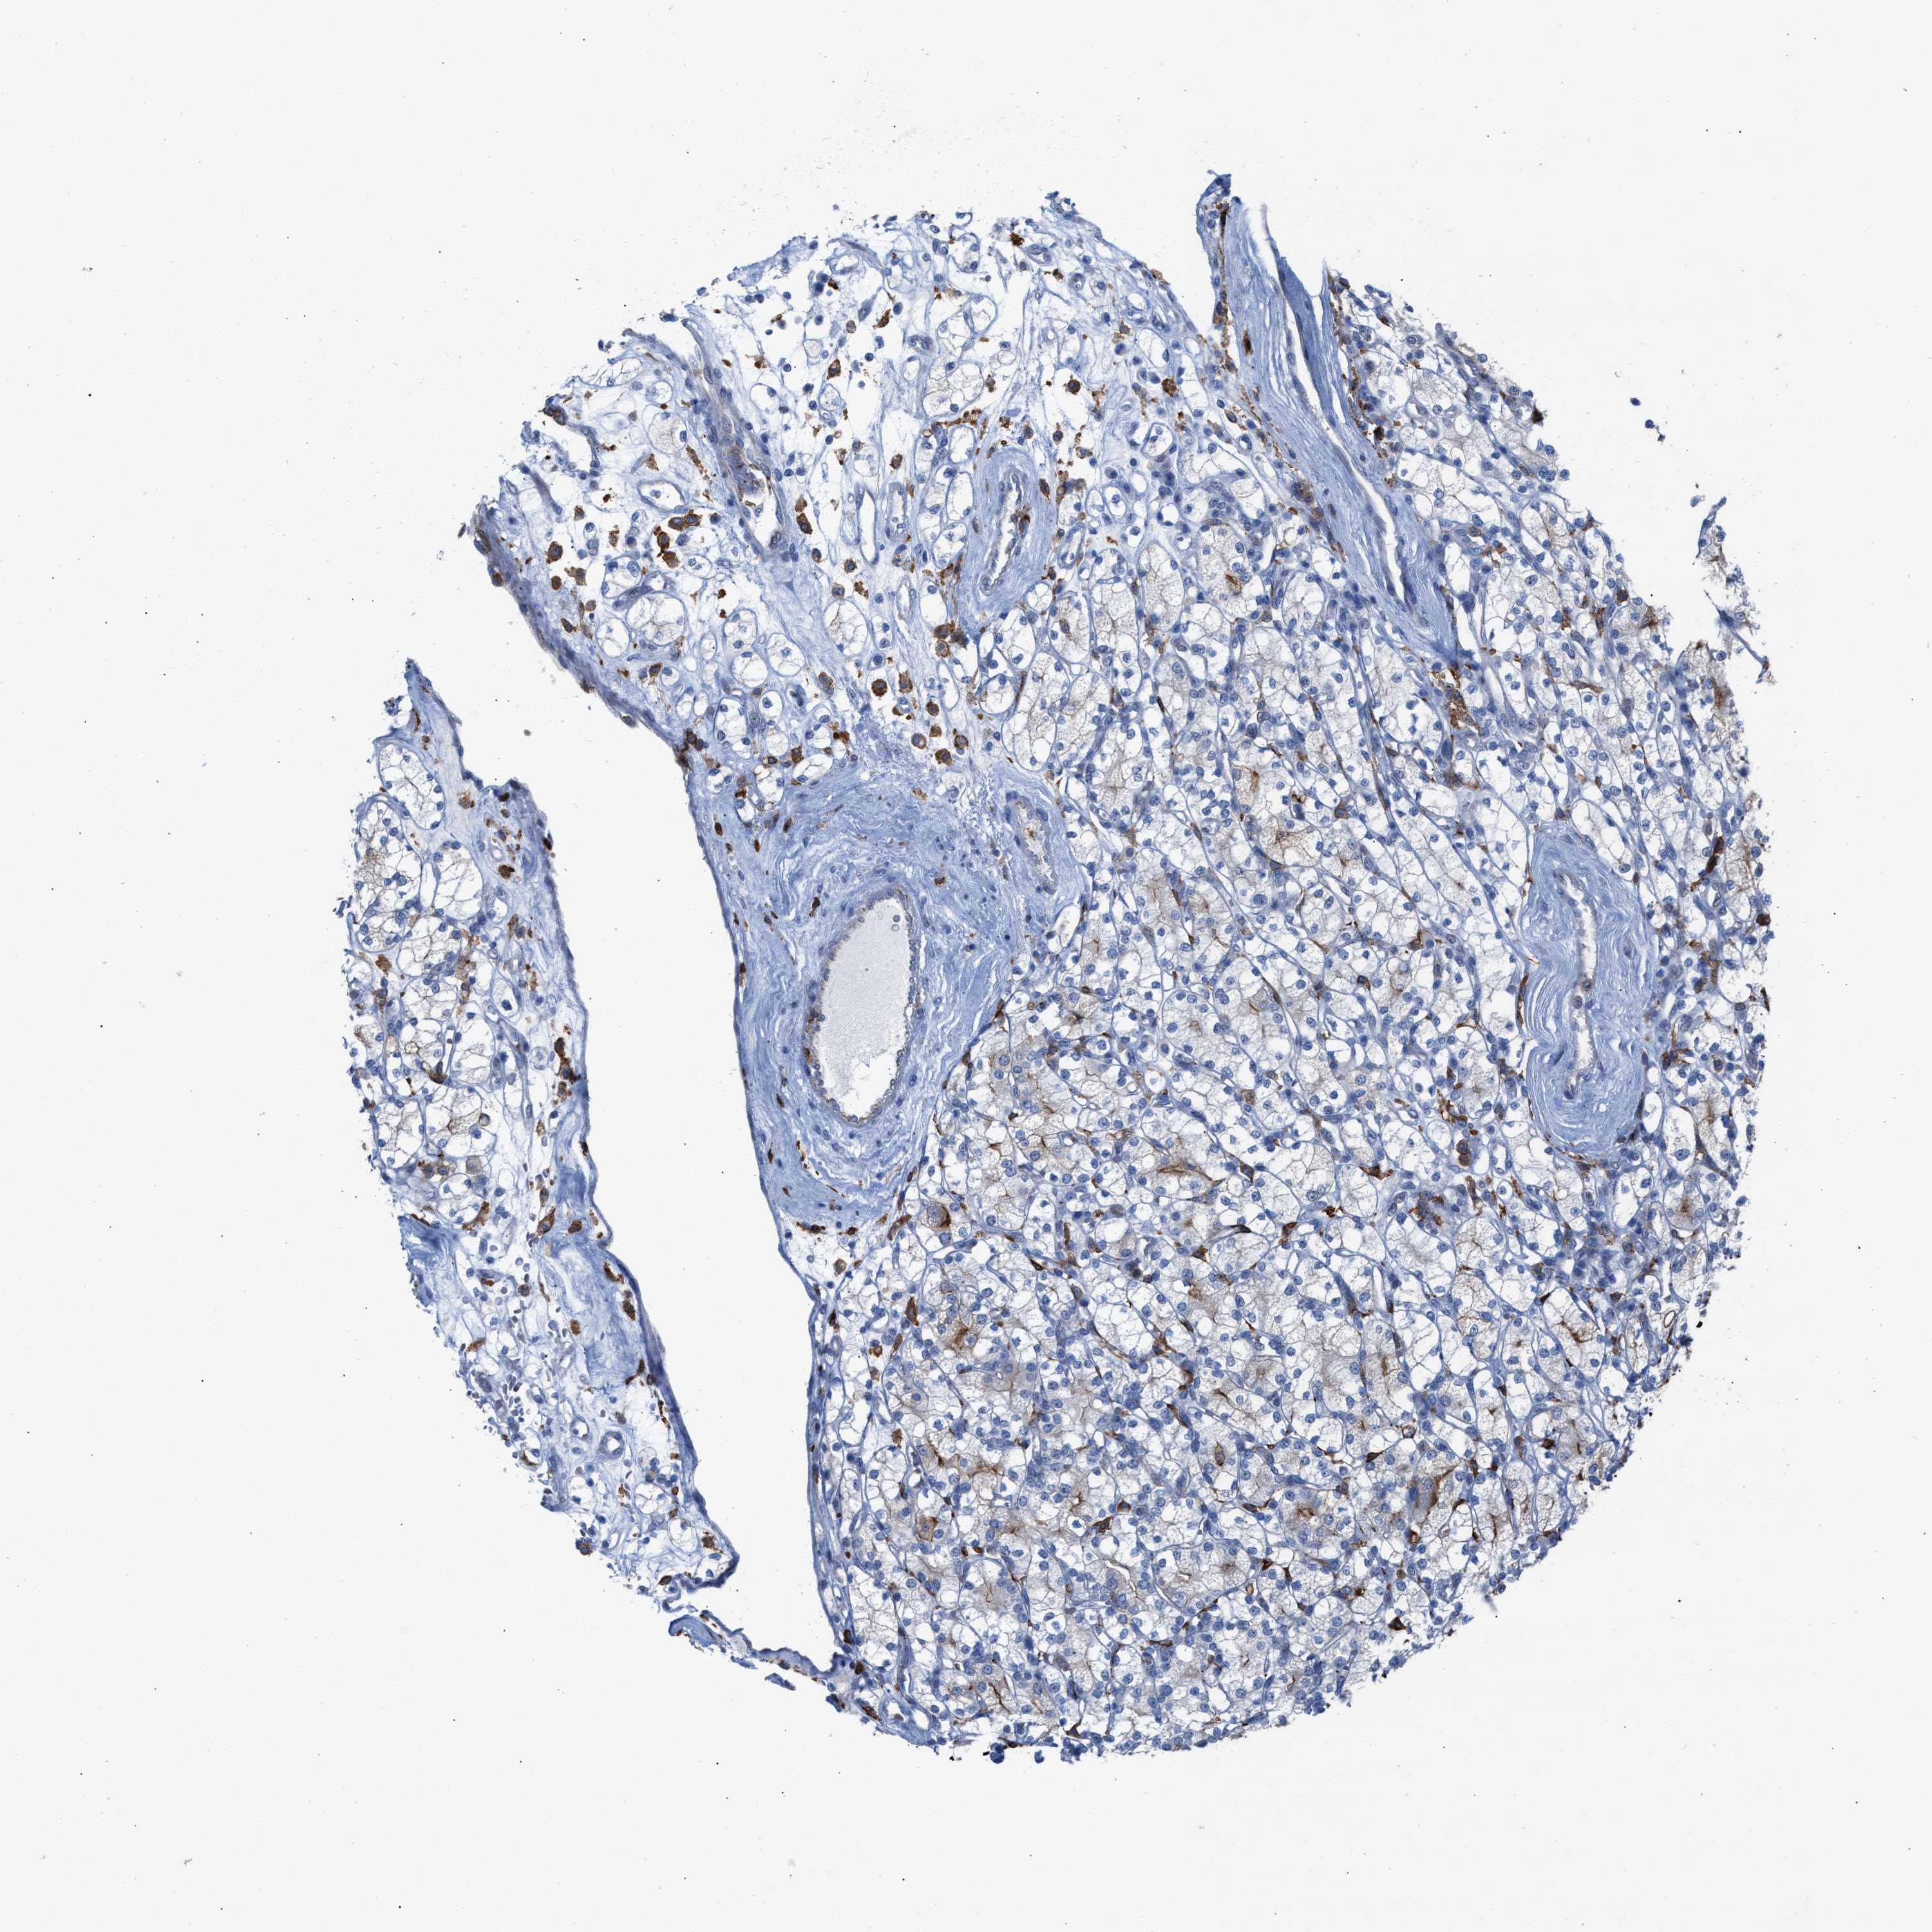

KIDNEY RENAL CLEAR CELL CARCINOMA (VALIDATION) - Interactive survival scatter ploti

The Survival Scatter plot shows the clinical status (i.e. dead or alive) for all individuals in the patient cohort, based on the same data that underlies the corresponding Kaplan-Meier plots. Patients that are alive at last time for follow-up are shown in blue and patients who have died during the study are shown in red.

The x-axis shows the expression levels (FPKM) of the investigated gene in the tumor tissue at the time of diagnosis. The y-axis shows the follow-up time after diagnosis (years). Both axes are complimented with kernel density curves demonstrating the data density over the axes. The top density plot shows the expression levels (FPKM) distribution among dead (red) and alive patients (blue). The right density plot shows the data density of the survived years of dead patients with high and low expression levels respectively, stratified using the cutoff indicated by the vertical dashed line through the Survival Scatter plot. This cutoff is automatically defined based on the FPKM cutoff that minimizes the p-score. The cutoff can be changed by dragging the vertical line or by entering a cutoff value in the square labeled "Current cut-off".

Under the Survival Scatter plot the p-score landscape (black curve; left axis) is shown together with dead median separation (red curve; right axis). Dead median separation is the difference in median mRNA expression between patients who have died with high and low expression, respectively. It is calculated as follows: median FPKM expression of dead patients with high expression - median FPKM expression of dead patients with low expression. This is intended to aid the user in visually exploring custom cutoffs and the associated p-scores and dead median separation.

Individual patient data is displayed and can be filtered by clicking on one or more of the category buttons on the top of the page. Categories describing expression level and patient information include: high, low, alive, dead, female, male and tumor stages. The scale of the x-axis can be toggled between linear and log-scale by clicking on the "x log" button. Mouse-over function shows TCGA ID, patient information and mRNA expression (FPKM) for each patient.

& Survival analysisi

Kaplan-Meier plots summarize results from analysis of correlation between mRNA expression level and patient survival. Patients were divided based on level of expression into one of the two groups "low" (under cut off) or "high" (over cut off). X-axis shows time for survival (years) and y-axis shows the probability of survival, where 1.0 corresponds to 100 percent.

SLC47A1 is validated prognostic, high expression is favorable in Kidney Renal Clear Cell Carcinoma (validation)

: 27.71

Average pTPM 123.3

Number of samples 100